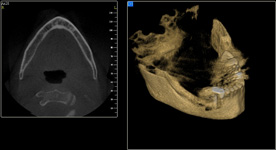

Nejčastější oblastí pro doplnění kosti je čeleni dutina horní čelisti.

Tento výkon se nazývá sinus lift - aplikace kostního granulátu do čelistní dutiny

Při ztrátě molárů a premolárů v horní čelisti a jejich náhradě implantáty se často setkáváme s nedostatečnou

vertikální nabídkou kosti pod čelistní dutinou, často doprovázenou i nedostatečnou horizontální nabídkou a sníženou kvalitou kosti (v oblasti 2. premoláru v 50%, v oblasti moláru až v 80% případů nedostatečná kostní nabídka)

Od roku 1985 je tento problém řešen augmentační operací nazývanou

sinus lift.

Jedná se o vyzvednutí membrány, která čelistní dutinu vystýlá, pod vyzvednutou membránou vznikne kapsa, kam se umístí augmentační materiál, do kterého se zavedou implantáty.

Vhojení implantátů se při této operaci prodlužuje na 6-12 měsíců.